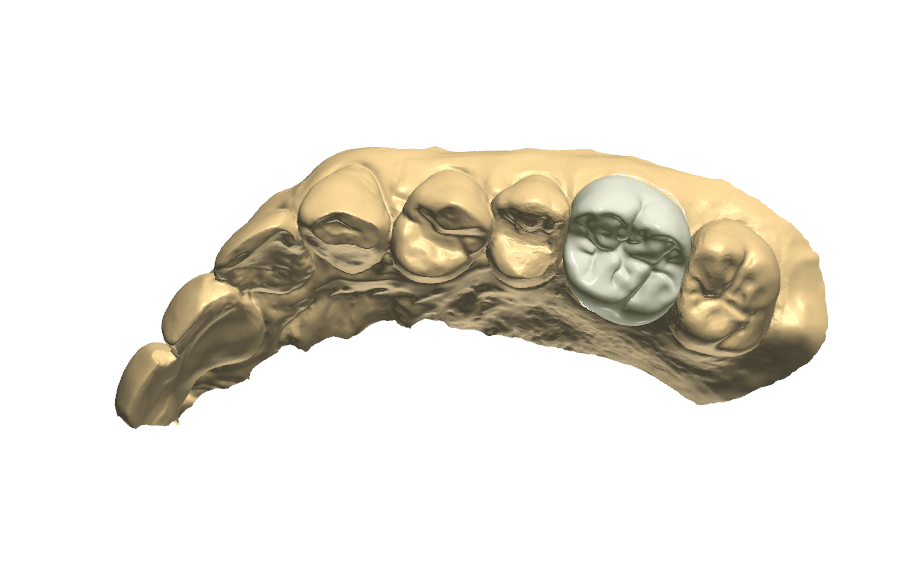

拔完牙後一個月,看傷口癒合情況,因兩顆門牙缺牙太久,齒槽骨流失比較多,醫師建議補骨跟植牙同時進行,植入三根牙根,位置分別在於右邊側門牙一顆,右邊正門牙和左邊側門牙。

再用左邊側門牙牙套搭橋到右邊正門牙牙套(三顆相連),右邊側門牙獨立做牙套。使門面變好看,說話也不會漏風。